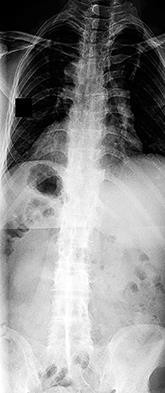

A 12-year-old premenarchal female is evaluated for a right thoracic prominence. Standing radiographs reveal a main thoracic curve of 32 degrees.

Her Risser stage is 0. Based on the Bracing in Adolescent Idiopathic Scoliosis Trial (BRAIST), which of the following factors has the most significant dose-dependent correlation with the success of bracing in preventing curve progression to surgical thresholds?